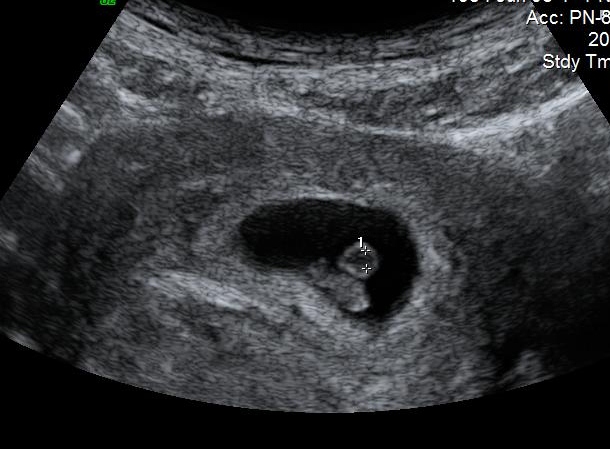

Hi everyone! This is my 7 week abdominal ultrasound. Can anyone help me with the gender PLEASE?? Attachment 7981

Slight girl lean, this is a tricky image as it's pretty central..

I would lean girl

do you know if the image was flipped or not? If not, I would lean boy, as I think the placenta looks to the left of the picture, which would be the right of you body (image holding it upright on your stomach). But I'm not sure that is the placenta because usually this early the placenta is closer to the baby, which means the placenta would be on the right side of the picture (left side of the body) meaning girl.

Hard to say Ramzi is hard if you dont ask the tech which side it is on